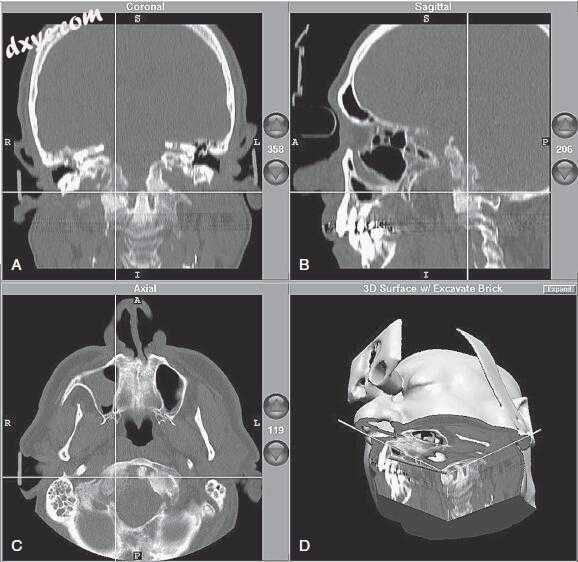

11.jpg

图-11. 术中计算机显示的导航图像。患者的CT图像显示在冠状面(A)、矢状面(B)和轴(C)和平面上;还示出三维剖视图(D)。在每个图像上,十字准线的交点指示导航探测器的位置。当探针在操作场内移动时,图像改变以反映探针的精确位置。在这种情况下,既有成骨细胞和溶骨性病变,并涉及枕骨髁内窥镜通过鼻腔接近,而不需要广泛的拆卸方法。该病变原来是来自先前肾细胞癌的转移。